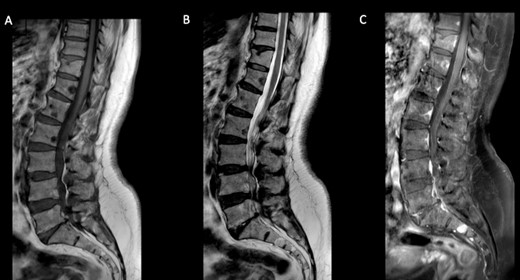

Further imaging tests showed multiple vertebral metastases but no organ dissemination (Fig. 5).

Spine MRI. Sagittal T1 (A) and T2 (B) reveal multiple hypo-intense vertebral metastases with enhancement (C).